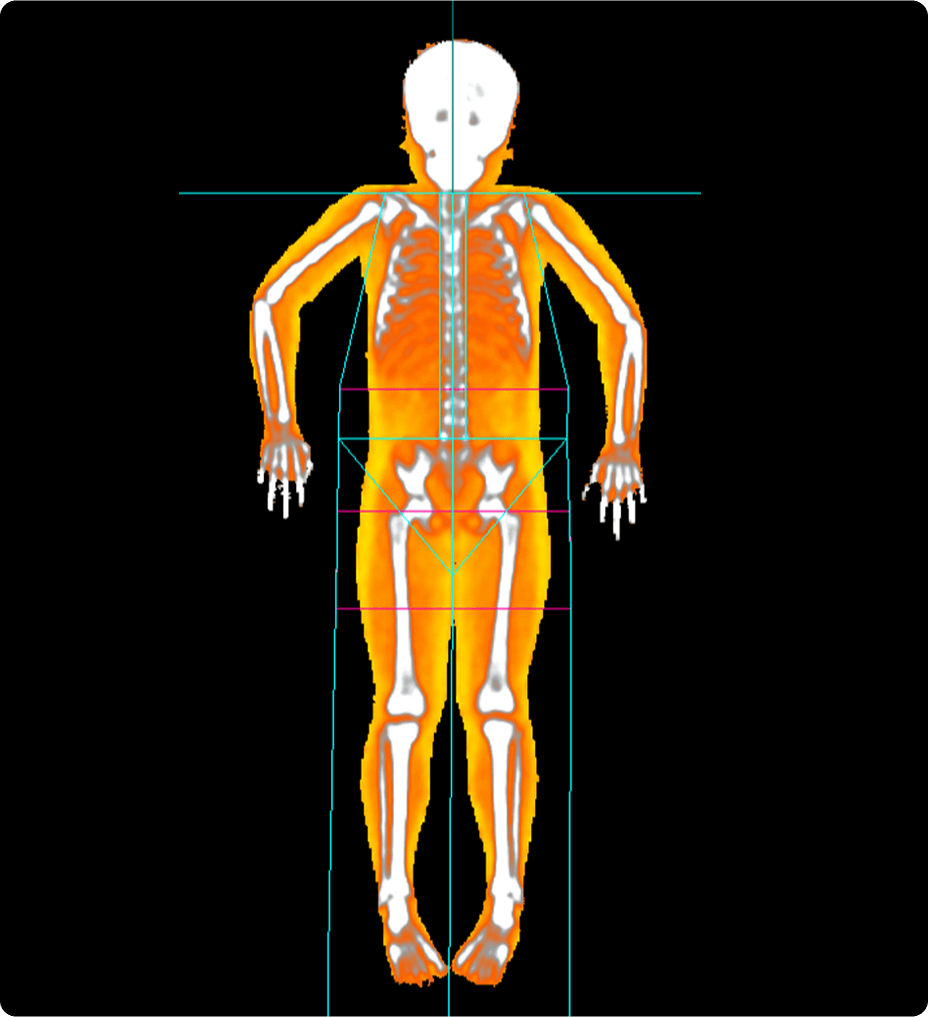

Acquisition plus intelligente avec DXAVision™

Les examens du corps entier constituent l’un des flux de travail DXA les plus chronophages. Avec ses deux nouvelles options d’acquisition, DXAVision™ permet de réaliser des acquisitions du corps entier avec une dose réduite jusqu’à 40 % plus rapides que les examens traditionnels du corps entier.1 DXAVision™ comprend également l’option Smaller Body Composition, conçue pour obtenir rapidement des résultats cohérents en plaçant automatiquement des points de coupe aux genoux et aux coudes.